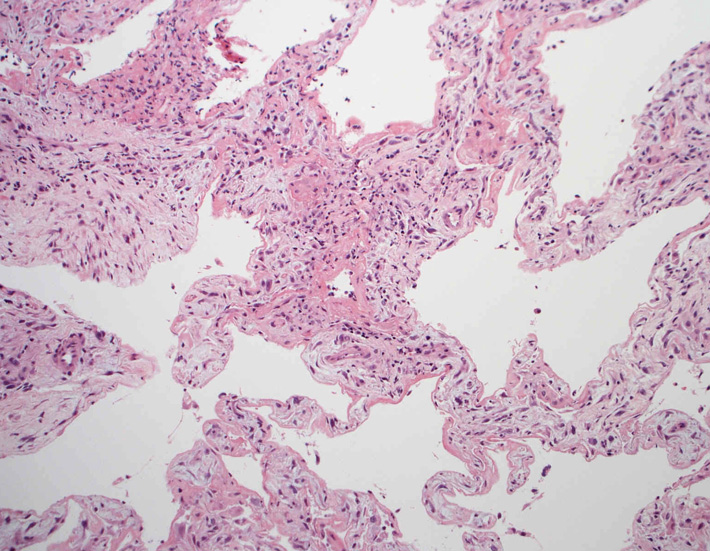

肺の病理所見

lung01.jpg

lung02.jpg

lung03.jpg

lung04.jpg

Fig.01Fig.02Fig.03Fig.04